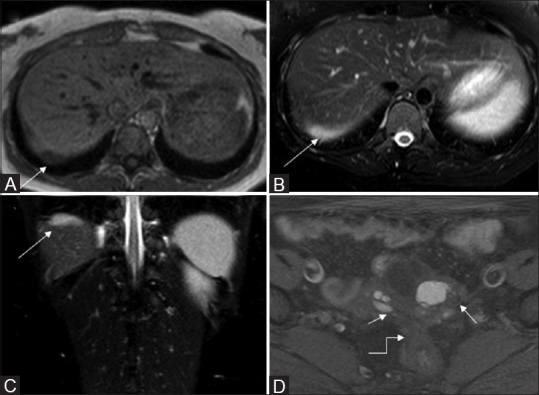

Extrapelvic endometriosis (EPE) is a rare entity which may potentially occur at any site. Symptomatic EPE is now increasingly being managed laparoscopically. Imaging is imperative in diagnosis as well as extent delineation prior to surgery. In addition to increasing the success rate of diagnostic laparoscopy, prior knowledge of EPE at certain sites may modify the standard surgical technique. We present here an unusual case of chronic pain in the right shoulder in a 26-year-old female caused by subdiaphragmatic endometriosis (SDE). It was noticed on conventional magnetic resonance imaging (MRI) sequences; however, due to the lack of the characteristic signal intensity, imaging findings were noncontributory. Diffusion-weighted imaging (DWI) facilitated its characterization and precisely mapped the extent of involvement. SDE should be suspected in young females presenting with cyclical shoulder pain. Due to nonspecific clinical features, it may remain undiagnosed. MRI is the imaging modality of choice in evaluation of EPE. Including DWI sequence in the MR protocol increases the diagnostic precision besides delineating the extent of involvement noninvasively.

摘要

盆腔外子宫内膜异位症(EPE)是一种罕见的病症,可能发生于任何部位。有症状的EPE目前越来越多地通过腹腔镜进行治疗。在手术前,影像学检查对于诊断以及明确病变范围至关重要。除了提高诊断性腹腔镜检查的成功率外,了解某些部位的EPE情况可能会改变标准手术技术。我们在此介绍一例26岁女性因膈下子宫内膜异位症(SDE)导致右肩慢性疼痛的罕见病例。在传统磁共振成像(MRI)序列上发现了病变;然而,由于缺乏特征性信号强度,影像学表现并无诊断价值。扩散加权成像(DWI)有助于对其进行特征性描述并精确确定受累范围。对于出现周期性肩部疼痛的年轻女性,应怀疑SDE。由于临床特征不具特异性,可能仍无法确诊。MRI是评估EPE的首选影像学检查方法。在MR检查方案中加入DWI序列,除了能无创地明确受累范围外,还能提高诊断准确性。